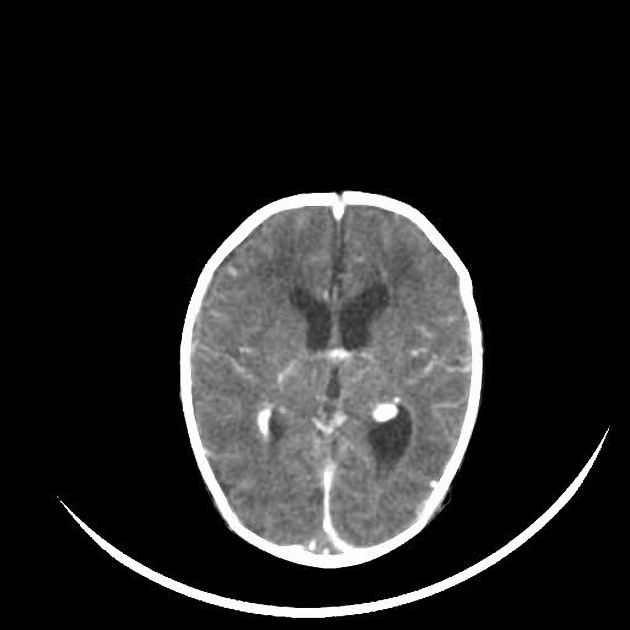

| Subarachnoid haemorrhage (SAH) | Hyperdensity in sulci, basal cisterns, or fissures. Diffuse SAH shows widespread cortical sulcal hyperdensity; localised SAH may be focal in a specific sulcus or cistern. |

| Cerebral venous thrombosis | May show “empty delta sign” with contrast (unenhanced thrombus centrally with enhancing sinus wall), venous infarcts, or haemorrhagic venous infarcts. |

- Haemorrhage: Hyperdense areas. Classify as epidural, subdural, intraparenchymal, or subarachnoid based on location and shape.